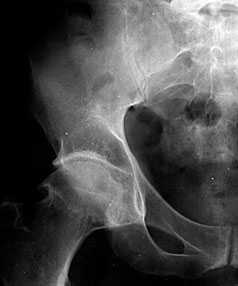

Рентгенологическая диагностика остеоартроза тазобедренных суставов

В начальных стадиях (1-2 стадии по Kellgren) ОА тазобедренных суставов при рентгенологическом исследовании определяются: незначительное сужение суставной щели, слабовыраженный субхондральный остеосклероз, точечные кальцификаты в области наружного края крыши вертлужной впадины (зачаток остеофитов), заострение краев ямки бедренной головки в области прикрепления круглой связки бедренной головки (рис. 1).

Рис. 1. Обзорная Rо-графия тазобедренного сустава в прямой проекции.

Деформирующий остеоартроз II ст. по Kollgren. Крупные остеофиты на краях суставных поверхностей. Грибовидная деформация бедренной головки

В поздних стадиях заболевания (соответствует 3-4 стадии ОА по Kellgren) отмечаются:

• прогрессирующее сужение суставной щели

• формирование различной формы и размеров остеофитов на краях суставных поверхностей вертлужной впадины, бедренной головки, отчего она со временем приобретает грибовидную форму. В средней части вертлужной впадины возможно формирование клиновидного остеофита, который может обусловить латеральное смещение бедренной головки

• углубление вертлужной впадины может быть связано с развитием остеофитов; протрузия ее возможна на фоне остеопороза или истончения костей, составляющих дно вертлужной впадины

• выраженный субхондральный остеосклероз. Проявляется в первую очередь в области крыши вертлужной впадины, затем в верхнем отделе бедренной головки

• в далеко зашедших случаях - уменьшение в объеме и уплощение суставной поверхности бедренной головки на фоне выраженной кистовидной перестройки костной ткани, чередующейся с участками субхондрального остеосклероза. Костные кисты могут быть единичными или множественными. Возникают они в верхней части вертлужной впадины или в зоне наибольшей нагрузки на суставную поверхность бедренной головки

• асептический некроз бедренной головки

• подвывихи бедренной кости чаще вверх и латерально, реже вверх и медиально

• уплотнение костной ткани и укорочение шейки бедренной кости.